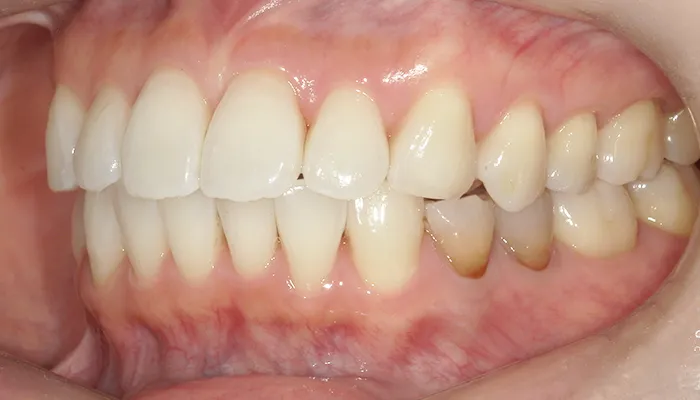

術前の口腔内写真

右下5番は大きく崩壊しており、保存不可能な状態でした。

また、下顎前歯部を中心に叢生があり、歯列が不均一でした。咬合関係が不安定で、清掃性も低下していました。

全体的に歯の色もやや黄みを帯びており、患者様からも審美的な改善希望が強くありました。